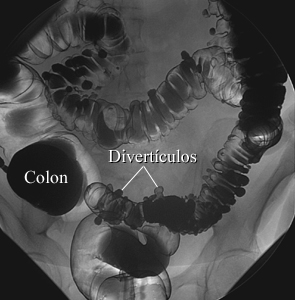

Enema de bario con contraste de aire